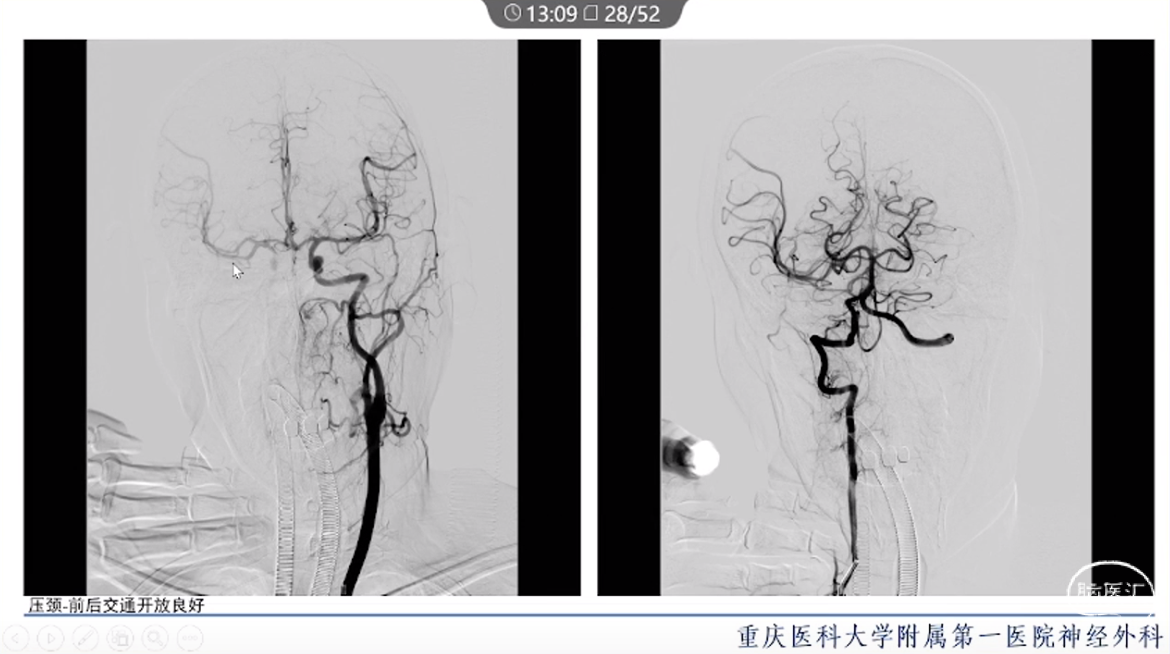

·颈内动脉颈段动脉瘤治疗方式有血管内治疗、外科手术和保守治疗。

·血管内治疗是最常见的治疗方式,随着血管内介入技术的发展和材料的进步,越来越多的动脉瘤可以通过血管内途径治疗。

·对于血管扭曲、血管直径大以及存在抗血小板禁忌的动脉瘤患者,特别是对于颈段大型或巨大型动脉瘤的治疗,常需要外科手术治疗。